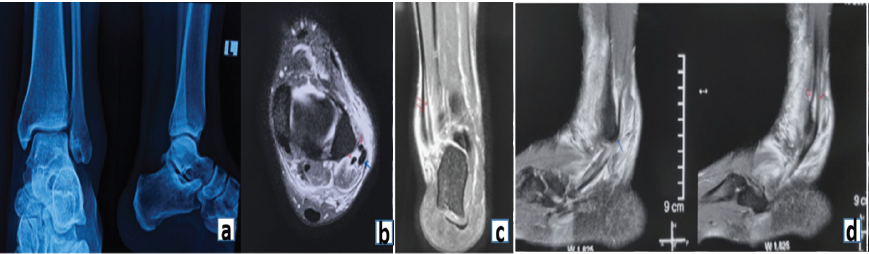

- Standard radiographs: Appeared normal (Fig. 1a)

- Dynamic ultrasound (USG): Demonstrated tendon subluxation, a longitudinal split tear of the PBT, and a SPR tear. USG also revealed peroneal tendon snapping over the fibula, confirming mechanical instability

- Magnetic resonance imaging (MRI): With greater displacement, a split tear of the peroneus brevis appeared as multiple subtendons. Subluxation of the split tendon was present, accompanied by a SPR tear. The split fragments of the peroneus brevis were displaced by the peroneus longus (Fig. 1b, c, d).

Figure 1: (a) Representative radiograph demonstrating normal appearance. (b) Transverse magnetic resonance imaging (MRI) image showing high signal intensity within the peroneus brevis tendon at the lateral malleolar level (red arrows). The peroneus longus tendon (blue arrows) appears normal. (c) Coronal MRI image demonstrating a longitudinal tear in the peroneus brevis tendon. (d) Sagittal MRI image demonstrating the longitudinal tear in the peroneus brevis tendon (red arrows) and a normal peroneus longus tendon (black arrow).